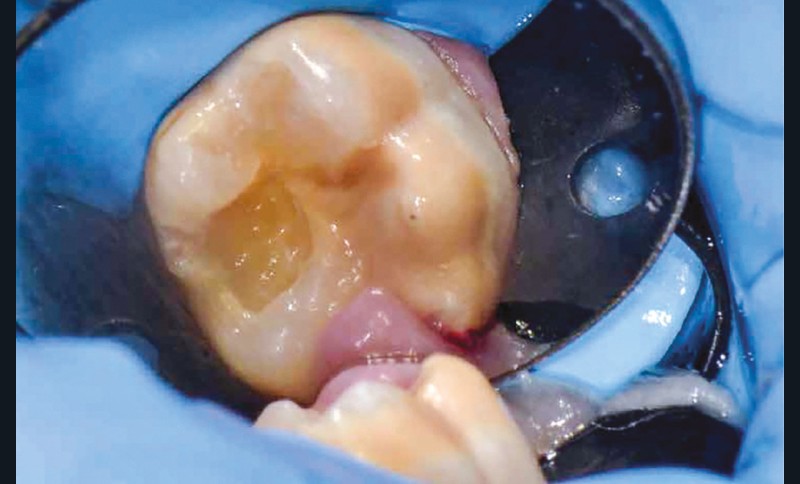

La difficulté anesthésique est systématique sur les molaires atteintes. En effet, les défauts de structures amélaires se traduisent par un émail poreux où les tubuli dentinaires sont larges (immaturité) et se retrouvent exposés. L’inflammation pulpaire chronique rend ainsi le silence opératoire difficile à obtenir.

Lisa est une jeune patiente de 10 ans, atteinte d’une MIH sévère sur les premières molaires mandibulaires 36 et 46 (fig. 1 et 2). Elle présente une sensibilité exacerbée au froid en regard des zones molaires entraînant un brossage approximatif.

Il a été décidé de réaliser des coiffes préformées métalliques sur les premières molaires permanentes pour supprimer les sensibilités et restaurer les fonctions mécaniques. Au regard de l’immaturité des tissus parodontaux et de l’anxiété de Lisa, la réalisation d’onlays n’a pas été envisagée.

Afin d’optimiser les séances de soins, l’anesthésie intra-osseuse par injection électronique a été réalisée avec le Quicksleeper 5® dans les deux secteurs (fig. 3 et 4) afin de permettre la réalisation des coiffes préformées métalliques sur 36 et 46 dans la même séance (fig. 5 à 7). Il aurait été difficilement envisageable de réaliser les coiffes dans la même séance en utilisant une anesthésie tronculaire dans chaque secteur.